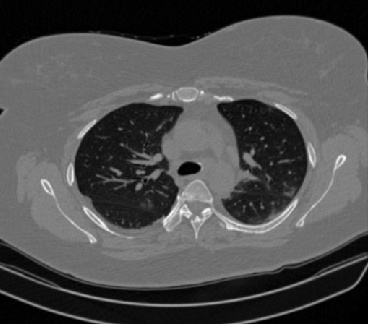

Figure 1 shows four CT scan slices, two from a non-COVID-19 CT scan, on the left and two from a COVID-19 scan, on the right. Bilateral ground glass regions are seen especially in lower lung lobes in the COVID-19 slices.